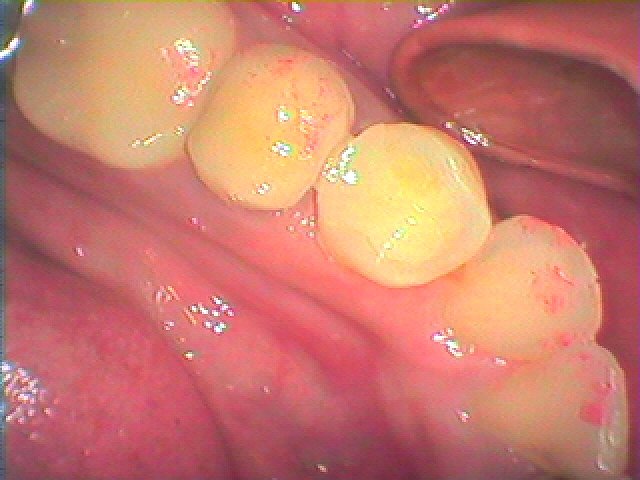

左下5番 何もしなくても痛くなってきたとのこと|お知らせ |広島市安佐南区の歯科医院 左下5番 何もしなくても痛くなってきたとのこと トップ お知らせ・ブログ お知らせ 左下5番 何もしなくても痛くなってきたとのこと 左下5番 何もしなくても痛くなってきたとのこと 誰が見てもよくわかる大きな穴が開いています 側面から見ると大きさがわかります レントゲンでも神経に虫歯がつながってきています 麻酔をかけて注意深く虫歯を除去していきました 最終的に薬を先まで詰めていきました 中を樹脂にて固めていきました セレックセラミックにて修復しています Web診療予約 初めての方へ 選ばれ続ける理由 院内設備について 歯が痛いしみる一般歯科 歯がぐらぐらする歯周病 健康な歯を保ちたい予防歯科 子供の虫歯予防をしたい小児歯科 銀歯をセラミックに審美歯科 白い歯を目指しませんか?ホワイトニング 矯正専門医がいるので安心矯正歯科 抜けた歯を補いたいインプラント・入れ歯 医院案内 スタッフ紹介 メリィハウス歯科クリニックオフィシャルホームページ ラベンダー歯科クリニックオフィシャルホームページ お知らせ・ブログ ホーム 診療科目 一般歯科 歯周病治療 予防治療 小児歯科 審美治療 ホワイトニング 矯正歯科 入れ歯・インプラント マウスピース矯正 初めての方へ 院長・スタッフ 設備紹介 医院案内・アクセス メニューを閉じる